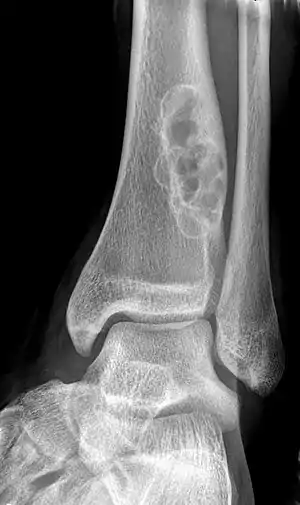

| X-ray of nonossifying fibroma of distal tibia. | |

Diagnosis is by X-ray or MRI, usually when investigating a person for something else.[2] Medical imaging typically shows a well defined radiolucent lesion, with a distinct multilocular appearance, sometimes looking like bubbles.[2] It is usually around 1-2cm in size, but be as large as 7cm.[3] They consist of foci consist of collagen rich connective tissue, fibroblasts, histiocytes and osteoclasts.[2] Usually no treatment is required.[1] Surgical curettage and bone grafting may be required if it is large.[3]

It is usually diagnosed by x-ray or MRI, when investigating another problem.[1] The tumor presents as a well defined radiolucent lesion, with a distinct multilocular appearance, sometimes looking like a "soap bubble".[5] If small and no symptoms, then biopsy is not needed.[1]